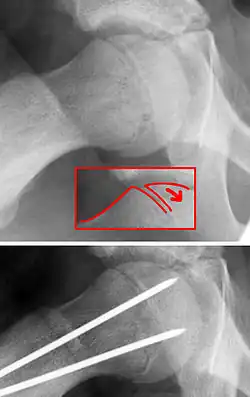

| X-ray showing a slipped capital femoral epiphysis, before and after surgical fixation. | |

The disease can be treated with external in-situ pinning or open reduction and pinning. Consultation with an orthopaedic surgeon is necessary to repair this problem. Pinning the unaffected side prophylactically is not recommended for most patients, but may be appropriate if a second SCFE is very likely.[11]

Once SCFE is suspected, the patient should be non-weight bearing and remain on strict bed rest. In severe cases, after enough rest the patient may require physical therapy to regain strength and movement back to the leg. A SCFE is an orthopaedic emergency, as further slippage may result in occlusion of the blood supply and avascular necrosis (risk of 25 percent). Almost all cases require surgery, which usually involves the placement of one or two pins into the femoral head to prevent further slippage.[12] The recommended screw placement is in the center of the epiphysis and perpendicular to the physis.[13] Chances of a slippage occurring in the other hip are 20 percent within 18 months of diagnosis of the first slippage and consequently the opposite unaffected femur may also require pinning.

The risk of reducing this fracture includes the disruption of the blood supply to the bone. It has been shown in the past that attempts to correct the slippage by moving the head back into its correct position can cause the bone to die. Therefore the head of the femur is usually pinned 'as is'. A small incision is made in the outer side of the upper thigh and metal pins are placed through the femoral neck and into the head of the femur. A dressing covers the wound.